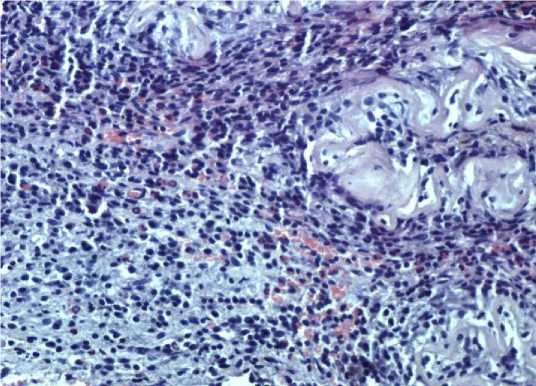

Эпителио-эпителиальный слой на гистологических препаратах II группы образцов замещен уплощенной гомогенной оксифильной структурой (рис. 2). В единичных сохранившихся эпителиоцитах наблюдается кариолизис и концентрация хроматина в виде конгломератов.

Компактный слой мембраны уплощен и гомогенно изменен. Количество фибробластов резко уменьшено, ядра сохранившихся из них имеют палочковидную форму или видны только как тени. Спонгиозный слой уплощен. Толщина препаратов лиофилизированной амниотической мембраны без обработки глицерином имеет среднее значение измерений (n=44) – 10,026 мкм.

Рисунок 2. Гистологический препарат амниотической мембраны, консервированной путем лиофильной сушки без обработки глицерином. Окраска гематоксилин-эозином. Ув. 400

Figure 2. Histological section of amniotic membrane preserved by lyophilization without glycerol pretreatment. Hematoxylin and eosin stain. Mag. 400